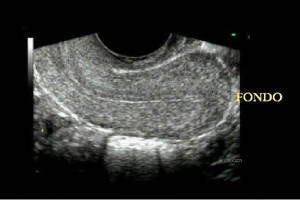

Diplomados en Ultrasonografía